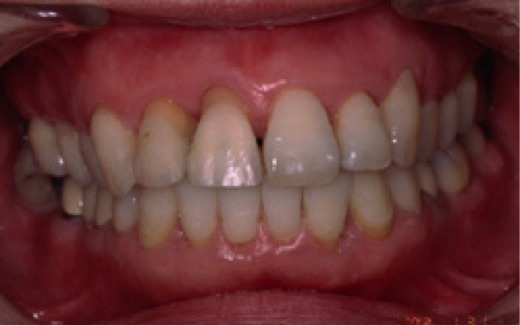

【女性(初診時37歳)非喫煙者】

約4ヶ月にわたる初期治療の結果、写真のように健康な歯周組織に回復しました。歯周ポケットはほぼ3mm以内です。この後、さらなる予防のために歯並び矯正治療を行いました。

術後の状態です。歯並びもよくなり、患者さんも満足されました。